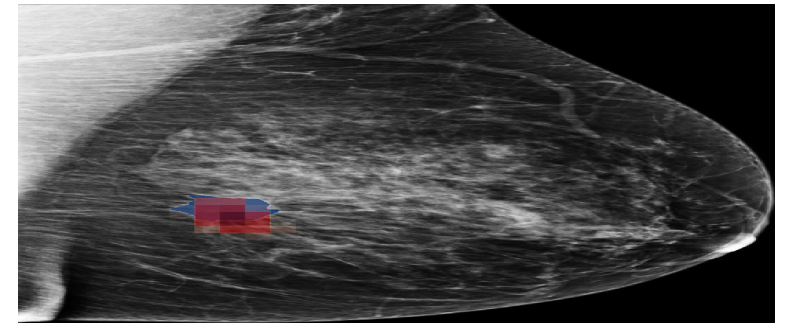

Refer to caption

(a) NYUtr\mathcal{M}_{\mathrm{NYU}}^{\mathrm{tr}}

(b) NYUtr\mathcal{M}_{\mathrm{NYU}}^{\mathrm{{}^{\prime}tr}}

(c) NYUtt\mathcal{M}_{\mathrm{NYU}}^{\mathrm{{}^{\prime}tt}}

Figure 9: Saliency maps generated by NYUtr\mathcal{M}_{\mathrm{NYU}}^{\mathrm{tr}}, NYUtr\mathcal{M}_{\mathrm{NYU}}^{\mathrm{{}^{\prime}tr}}, NYUtt\mathcal{M}_{\mathrm{NYU}}^{\mathrm{{}^{\prime}tt}} models on a sample from the CSAW dataset. Blue regions represent the ground truth annotations, while red regions highlight the saliency maps corresponding to the malignant class.

Saliency maps in Figure 9, generated for a CSAW sample, further support this conclusion at a higher level. While the NYUtr\mathcal{M}_{\mathrm{NYU}}^{\mathrm{tr}} model accurately identified the relevant regions, the model evaluated on the altered input distribution (NYUtr\mathcal{M}_{\mathrm{NYU}}^{\mathrm{{}^{\prime}tr}}) failed to highlight the correct areas. Nevertheless, when test-time BN statistics were applied to the altered input (NYUtt\mathcal{M}_{\mathrm{NYU}}^{\mathrm{{}^{\prime}tt}}), the model’s ability to localize the correct regions was restored.